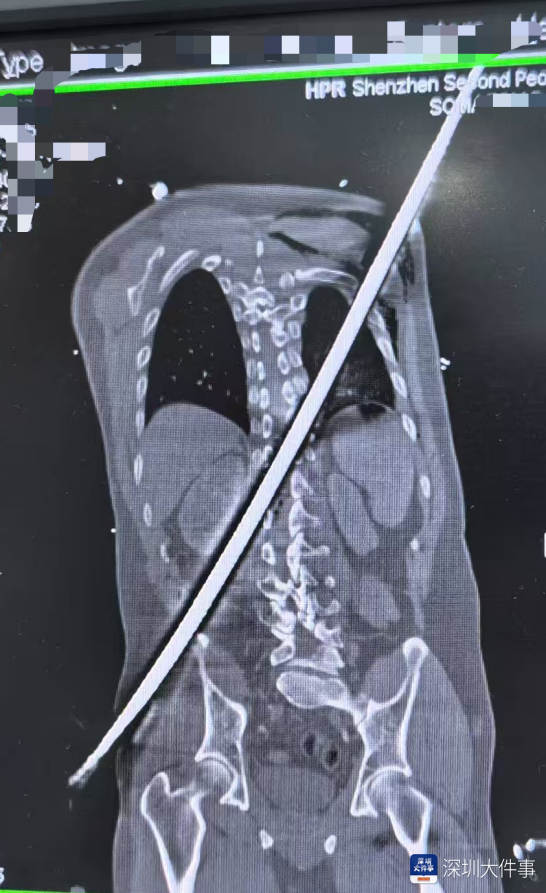

全身CT扫描精准勾勒出钢筋在体内的“行走路径”:钢筋险之又险地穿过腹膜后间隙,击穿胸腰段脊柱椎管,最终穿入胸腔,其路径紧贴肾脏、大血管等关键脏器——每一次心跳,都可能让钢筋锋刃与血管发生摩擦,引发灾难性大出血。